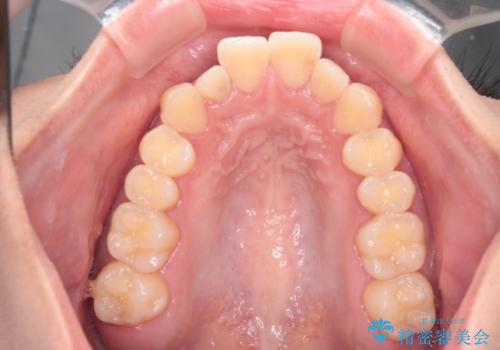

【インビザライン】反対咬合を治したい

- 前歯の反対咬合を主訴に来院されました。

インビザラインにて歯列弓の拡大により叢生の改善を行うことができ、患者様にも満足していただました。